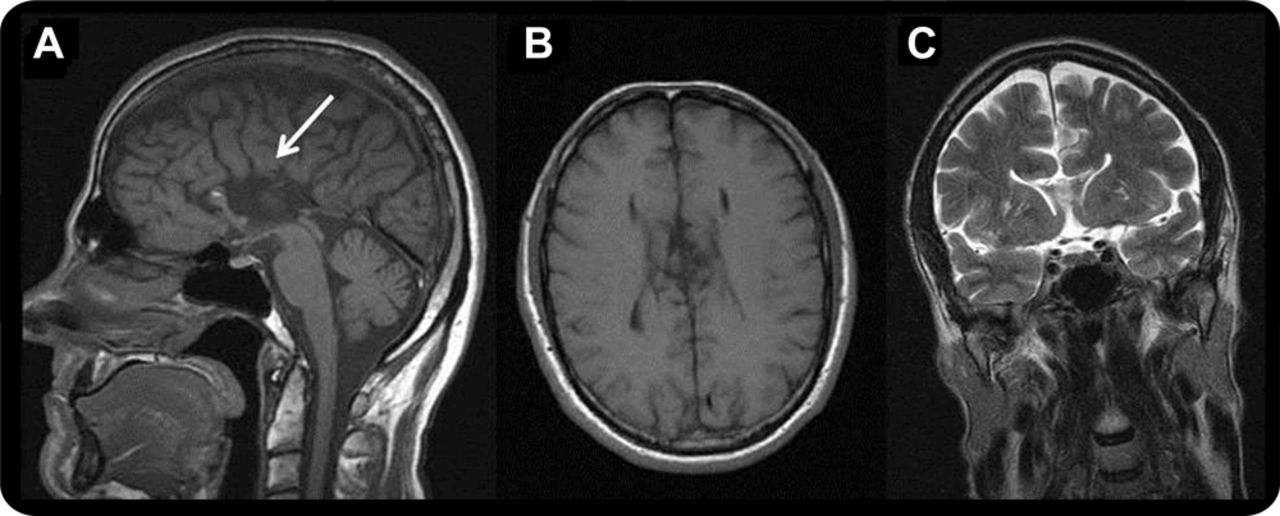

58岁的男人面对每日一小时的低体温、多汗、低血压。实验室研究的结果,包括促甲状腺激素,免费的甲状腺素,总/可利用睾酮、皮质醇,早上和尿同渗重摩,是正常的。核磁共振成像的大脑显示胼胝体发育不全(图A和B)与夏皮罗综合征一致。

图 核磁共振成像的大脑

(一)矢状t1和(B)轴向t1影像显示胼胝体发育不全(箭头所指)暗示夏皮罗综合症。没有注意到垂体异常。(C)冠t2加权图像显示海盗头盔或麋鹿头外观认为侧脑室的胼胝体的缺失。

夏皮罗综合征是一种罕见的疾病中描述少于60名患者。它由周期性低体温,多汗,胼胝体发育不全。1,2任何条件胼胝体发育不全导致侧心室承担海盗头盔外观(图C)。夏皮罗的低体温症综合征可能是由于下丘脑功能障碍和可能对可乐定。2